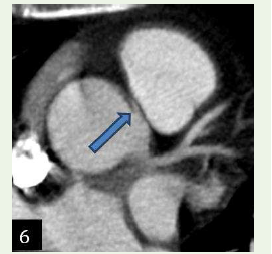

Case 3: A 45-year-old male smoker & alcoholic with c/o chest discomfort & mildly positive stress test demonstrated an anomalous origin of Right coronary artery from the le coronary sinus with malignant inter-arterial course.

Figure 6:Case 3: Maximum intensity projection reconstruction shows an

anomalous origin of Right coronary artery from the left coronary sinus with

Malignant inter-arterial course. Note the narrow caliber of origin of RCA.

Figure 7:3D volume rendered reformation shows an anomalous origin of

Right coronary artery from the left coronary sinus. Note the narrow caliber

of origin of RCA.